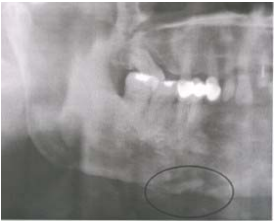

10. 如下圖所示,下列那一個診斷比較正確?

(A) Necrotizing fasciitis (B) Abscess (C) Osteomyelitis (D) Ludwig’s angina